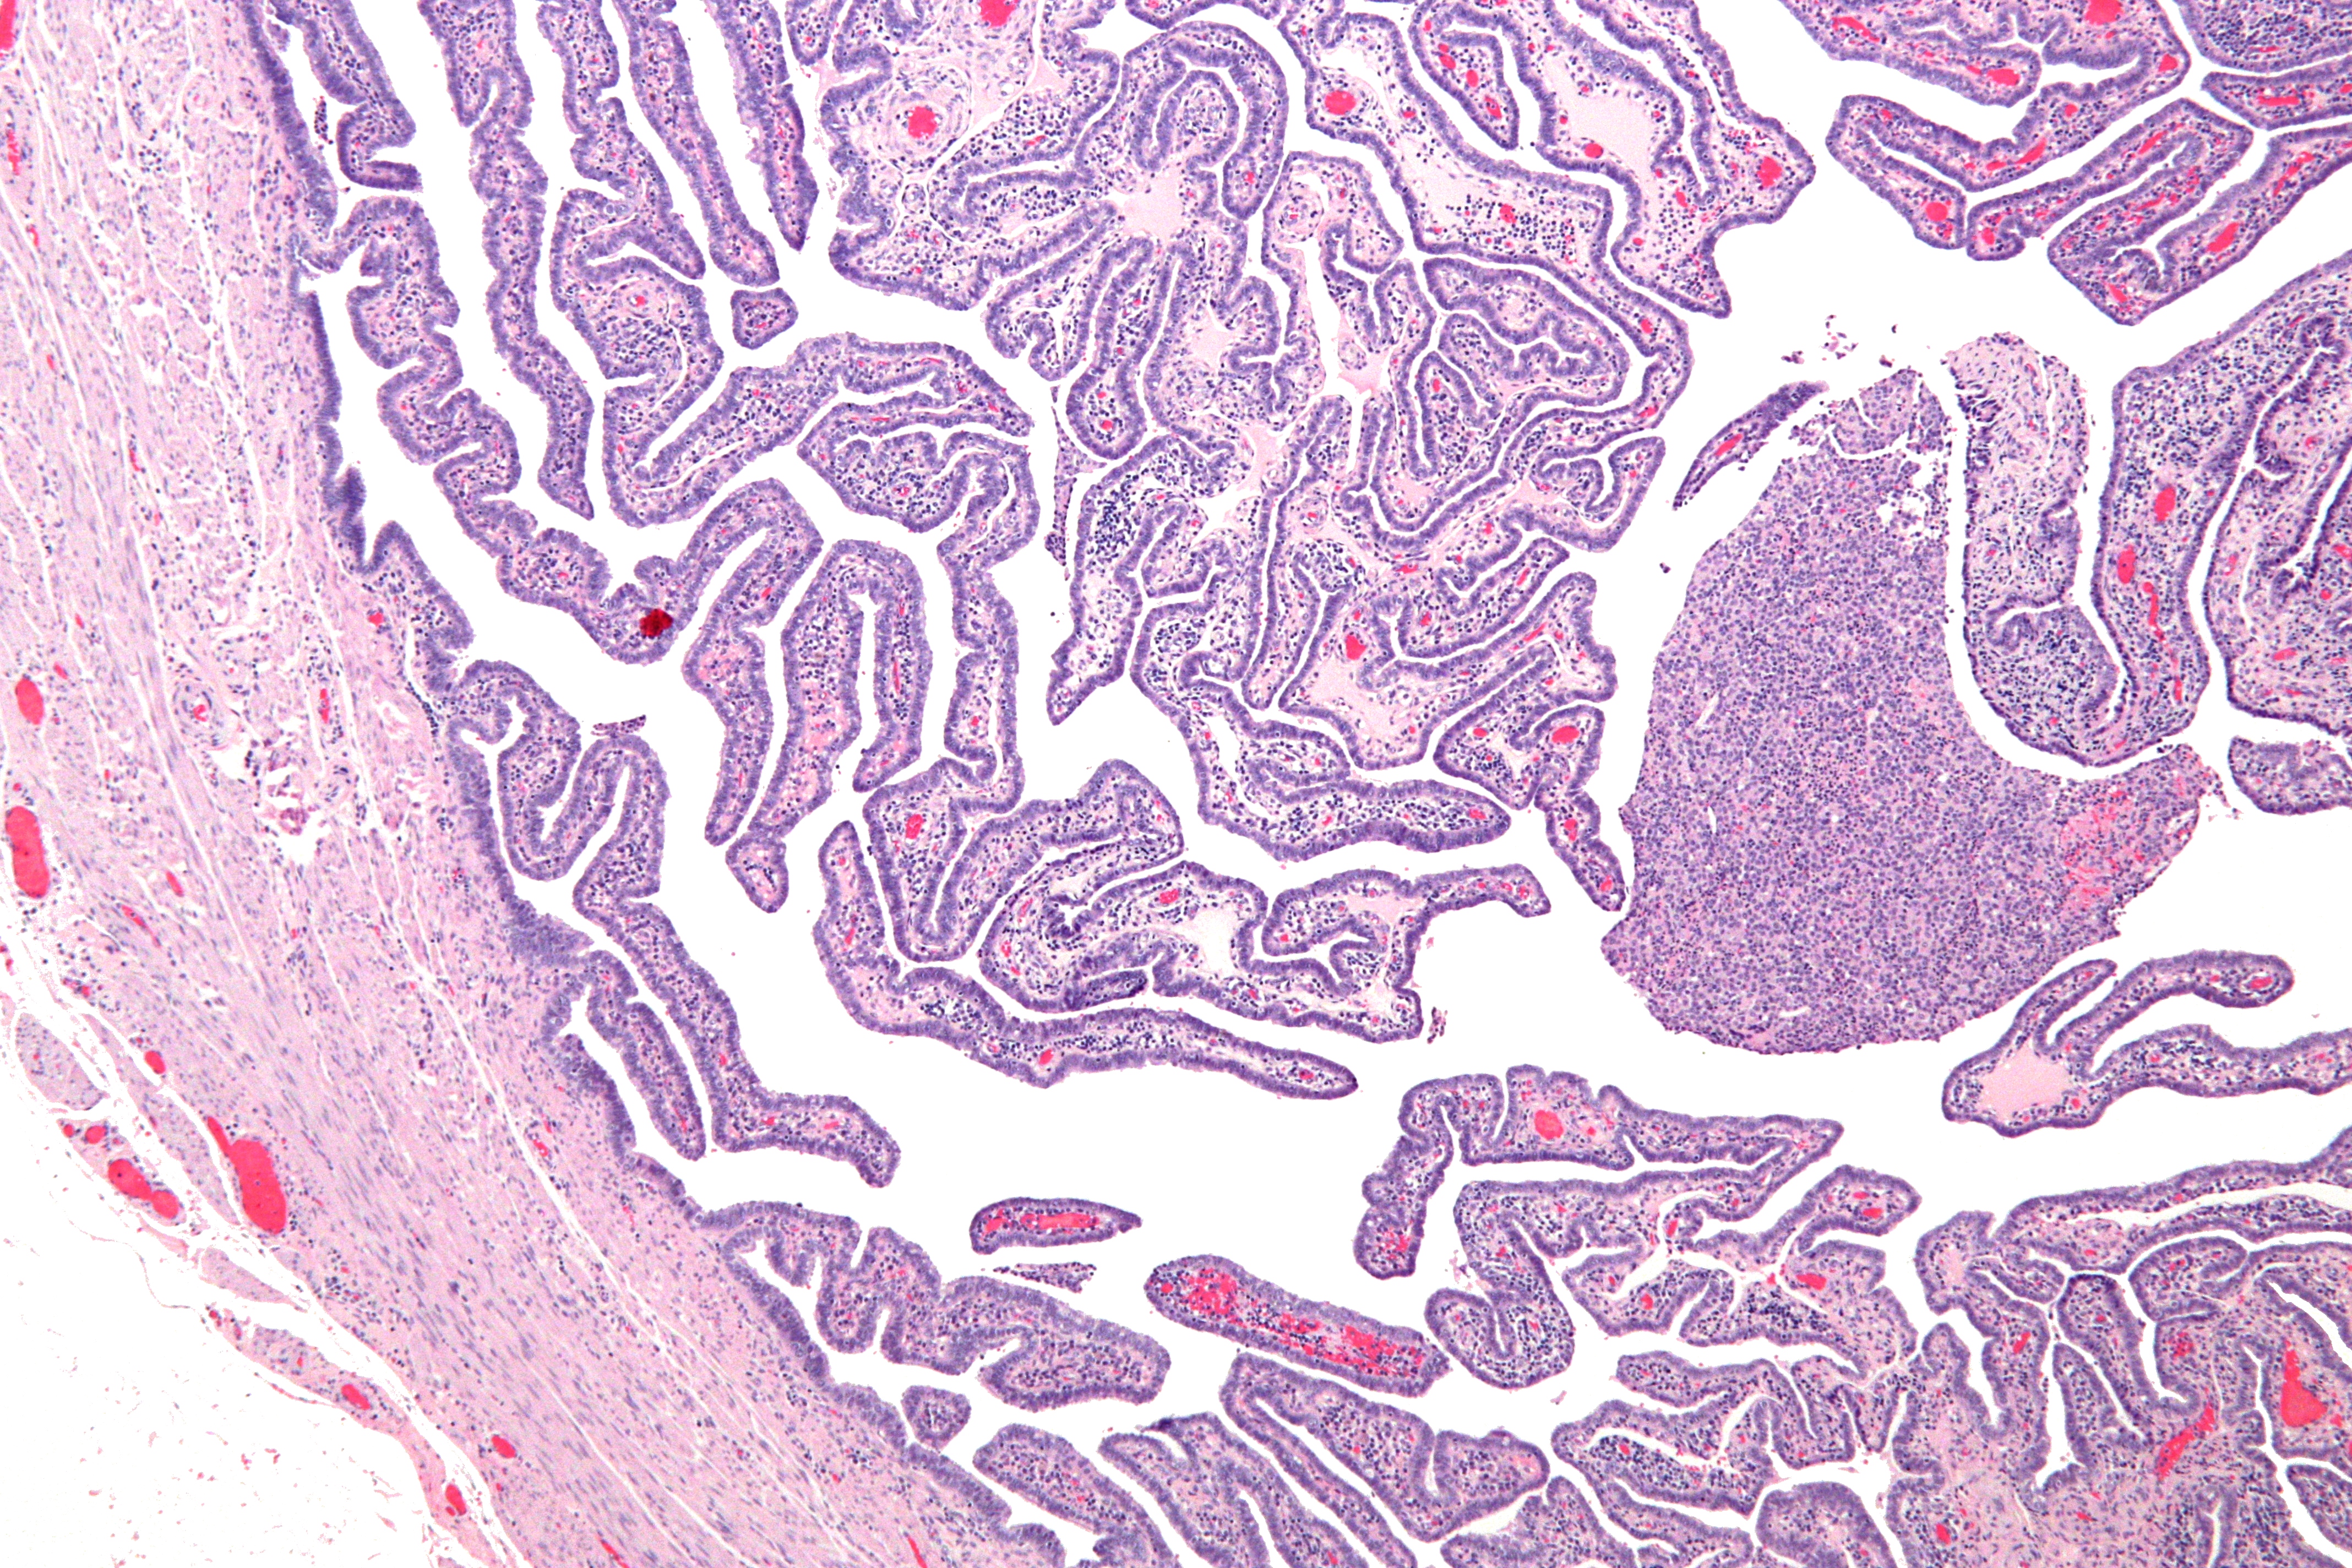

확정적 기준에는 조직병리학적 자궁내막염 증거, 두꺼워진 나팔관, 복강경 검사 소견이 포함된다. 그람 염색/도말은 드물고 비정형적이며 더 심각한 유기체의 식별에 결정적인 역할을 한다.[24] 이전 PID의 복강경 증거가 있는 환자의 2/3는 PID가 있다는 것을 알지 못했지만, 무증상 PID조차 심각한 해를 입힐 수 있다.